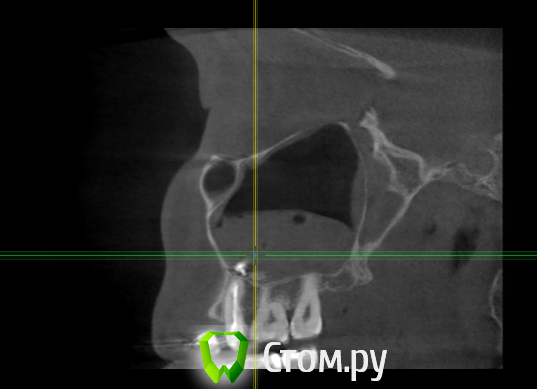

Force Опубликовано 6 апреля, 2014 Поделиться Опубликовано 6 апреля, 2014 пародонт, корни и гайморову пазуху Ссылка на комментарий

enka Опубликовано 16 апреля, 2014 Автор Поделиться Опубликовано 16 апреля, 2014 Уважаемые, ДОКТОРА! Что Вы видите на КТ? Подскажите...... Ссылка на комментарий